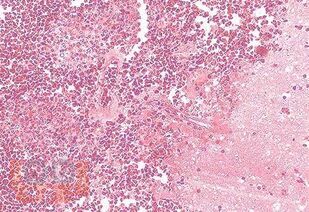

Материал пособия раскрывает патогенез лучевой болезни, ее стадии, судебно-медицинскую характеристику смертельных повреждений от действия ионизирующего излучения, судебно-медицинскую экспертизу трупа в случаях подозрения на насильственную смерть от действия лучевой травмы, особенности проведения судебно-медицинской экспертизы трупов лиц,

погибших при радиационных авариях в случаях массовой гибели людей, особенности изъятия и направление трупного материала на лабораторные исследования.